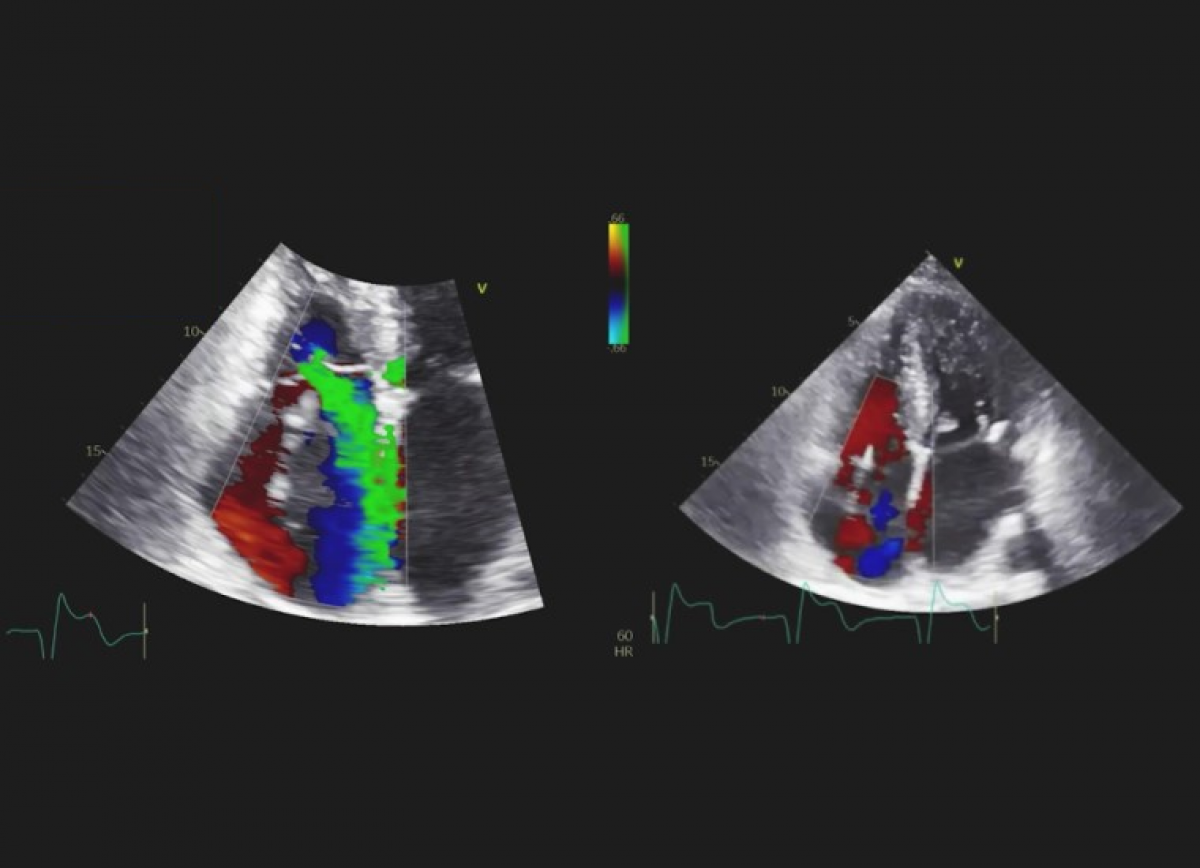

Pacjentka z kardiomiopatią przerostową, z napadowym migotaniem przedsionków, po implantacji ICD oraz przezskórnym zamknięciu uszka lewego przedsionka.

Kardiomiopatia przerostowa z zawężaniem drogi odpływu lewej komory. Ciężka niedomykalność trójdzielna.

Echokardiografia przezklatkowa i przezprzełykowa

Echokardiografia trójwymiarowa.

Ocena kardiomiopatii przerostowej.